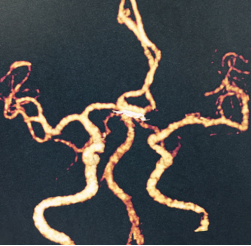

颅内动脉瘤(Intracranial Aneurysm, AN)是一种常见的出血性脑血管病,具有较高的死亡率和致残率。1)病情隐匿,很多情况下动脉瘤并不能有预期的得到诊断,除非动脉瘤压迫到了邻近的神经产生了明显的症状,从而间接提示动脉瘤的存在。2)病情凶险,脑动脉瘤的破裂可以导致致命的出血和脑损害,有1/3的人可能来不及救治,1/3送到医院后救治遗留有重残,仅1/3的病人可以恢复良好。该如何早期发现和处理脑动脉瘤呢? 作为脑血管病诊断的金标准是全脑数字血管造影术,但这是一种有创性检查,会给被检查者带来一定痛苦,因而不能够作为一种体检或筛查手段。而CT血管成像可以在早期发现颅内动脉瘤,这是一种无创性检查,其准确率可以达到97%左右;同时核磁共振血管成像也是一种无创而准确率很高的判断是否存在颅内血管瘤的检查方法,通过软件将脑里的血管重建出来,对于3mm以上的动脉瘤敏感性则高达97%,可以较好的显示动脉瘤的形态、大小及与载瘤动脉的关系。

对于偶然发现的动脉瘤是否需要立即处理目前学术界尚存在争议,但如果存在下列情况,即动脉瘤在随访过程中有增大或动脉瘤形状不规则,动脉瘤位于脑内,必要的医疗干预可以大大降低动脉瘤破裂的风险。颅内动脉瘤处理的方法有手术夹闭,血管内介入治疗,这两种方法各有利弊,要根据动脉瘤的具体形态和病人的状况而定,目前我院神经外科在史锡文主任带领下年夹闭动脉瘤300余例,对“巨大脑动脉瘤切除并血管重建术,复杂动脉瘤夹闭术,多发动脉瘤杂交手术”积累了大量经验。